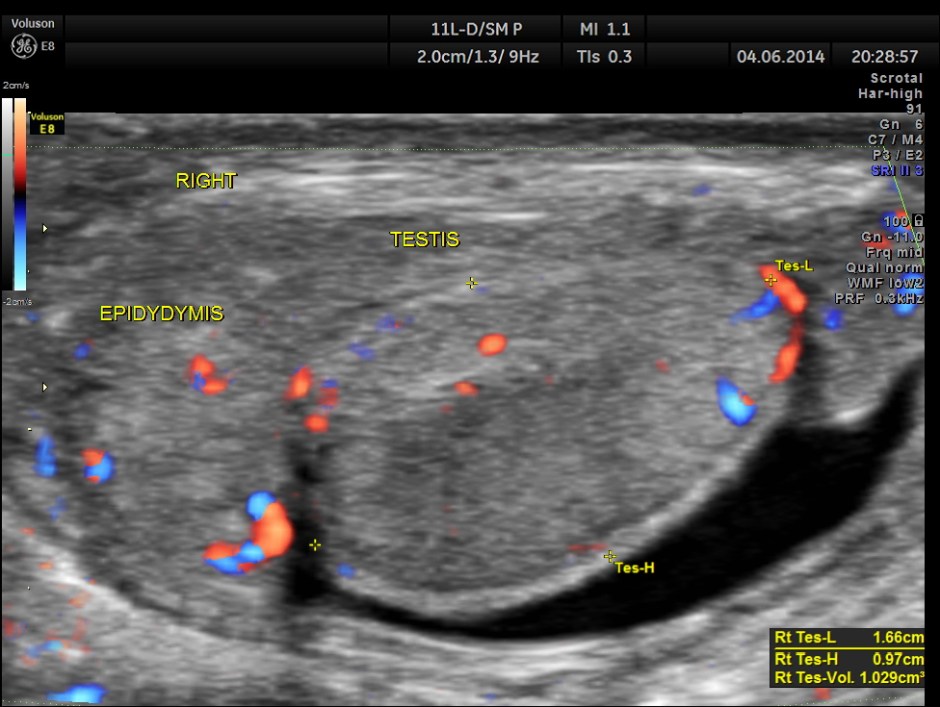

Rt Testis has normal appearance , with enlargement of the right epididymis . Colour flow imaging shows normal flow in the scrotum and increased flow in the epididymis , suggestive of acute inflammation – Acute Epididymitis.

The images of the left testis are given below for comparison.